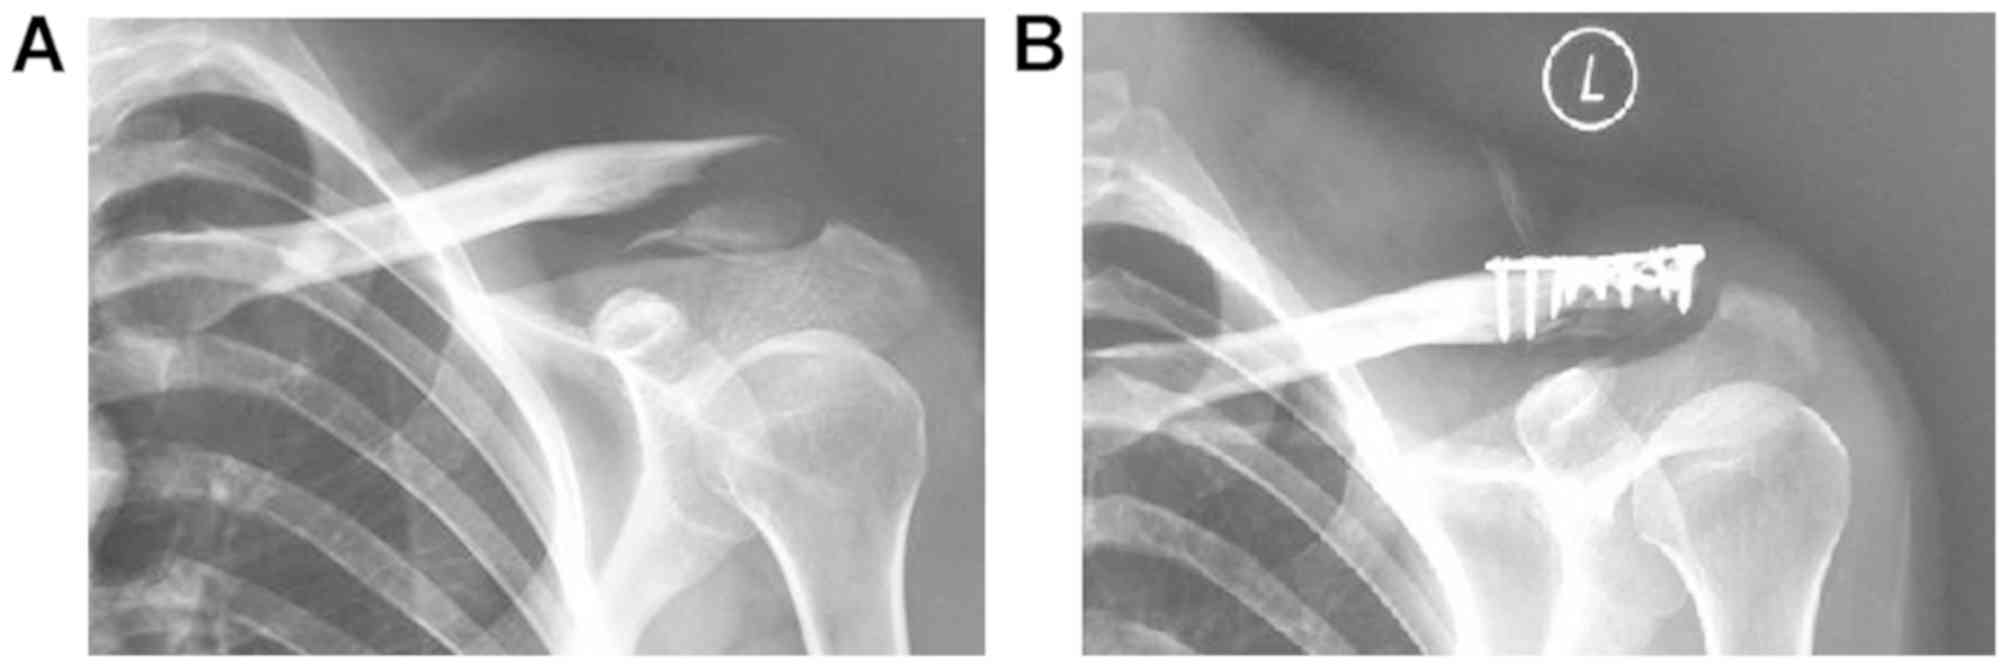

A 24 Year Old Male Patient Had A Left Distal Clavicle Fracture Treated Download Scientific Diagram

Distal clavicle fracture treatment. Non-operative Treatment of Acute Displaced Distal Clavicle Fractures. Twelve patients with Neer Type IIb distal clavicle fractures treated with anatomical locking plate fixation combined with suture anchor augmentation of the coracoclavicular ligament were retrospectively studied. It is recommended that you ice the fractured area for 15 to 20 minutes every two hours for as long as necessary to decrease the pain and swelling.

Treatment Of Neer Iib Distal Clavicle Fractures Using Anatomical Locked Plate Fixation With Coracoclavicular Ligament Augmentation Journal Of Hand Surgery